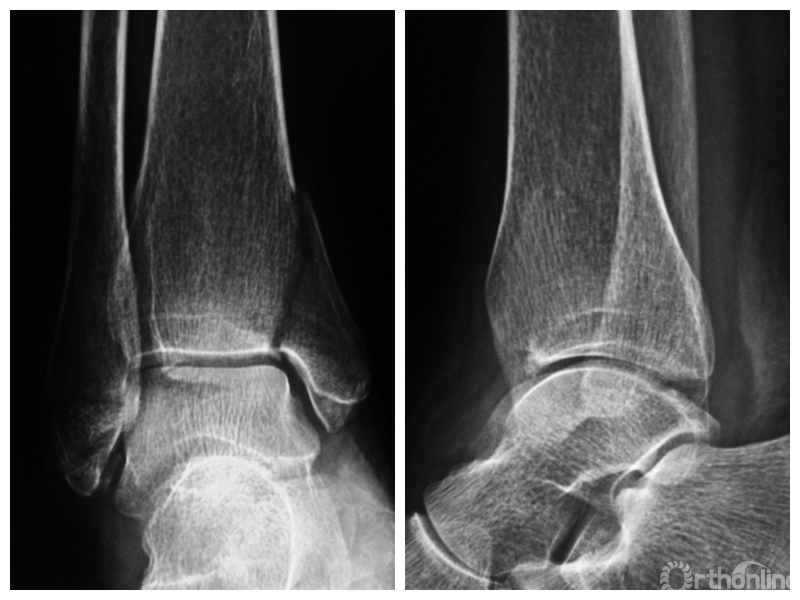

图1 支撑钢板固定组患者,女,63岁,右侧旋后-内收型II度踝关节骨折 a. 术前正侧位X线片;b. 术前CT;c. 术后2周正侧位X线片;d. 术后2年正侧位X线片

图1a 术前正侧位X线片

两组患者均获随访,支撑钢板固定组随访时间46~91,平均64.5个月;螺钉固定组随访时间44~86,平均59.5个月。支撑钢板固定组患者术后完全负重时间为(11.5±1.6)周,较螺钉固定组的(12.6±2.3)周显著缩短,比较差异有统计学意义(t=2.05,P=0.04)。X线片复查示,支撑钢板组均获解剖复位,均达愈合;螺钉固定组有20例获解剖复位,2例畸形愈合,1例不愈合,支撑钢板组骨折愈合时间为(11.5±1.6)周,螺钉固定组为(12.0±1.7)周,比较差异无统计学意义(t=1.06,P=0.30)。见图1、2。支撑钢板固定组3例(10%)、螺钉固定组4例(17.4%)发生创伤性关节炎,均采取保守治疗;两组比较差异无统计学意义(P=0.45)。